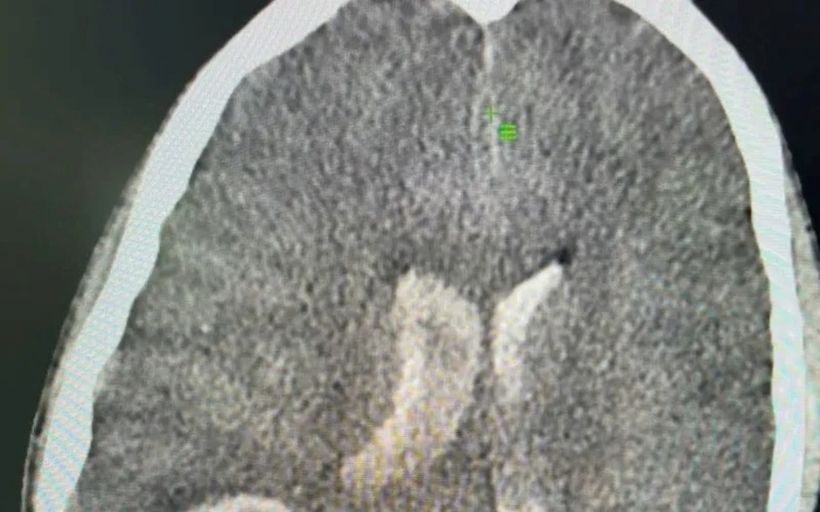

Tại Trung tâm Y tế Hồng Lĩnh (Hà Tĩnh), bệnh nhi được chỉ định chụp cắt lớp vi tính sọ não. Kết quả cho thấy bệnh nhi bị xuất huyết não lan vào não thất - một tình trạng cấp cứu nguy hiểm, có thể đe dọa tính mạng nếu không được xử lý kịp thời.

Bé trai được xác định xuất huyết não qua hình ảnh cắt lớp vi tính. Ảnh: Thời báo VTV